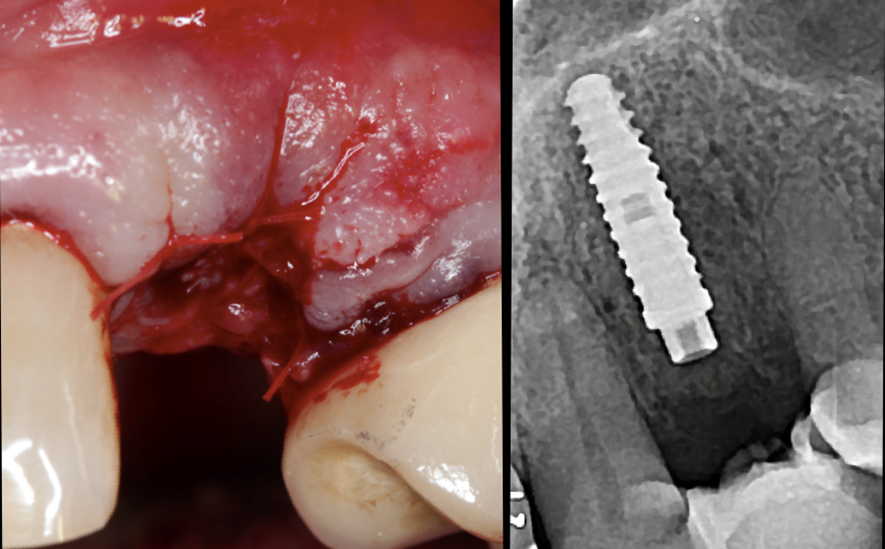

A seguir, as figuras 1 a 5 ilustram o caso:

Por outro lado, sabemos que quando obtemos uma estabilidade primária interessante (acima de 20N) e usamos biomateriais comprovadamente eficazes, os resultados para a implantação imediata associada com ROG são bastante promissores. Além da vantagem de se diminuir o número de cirurgias, temos também, a nosso favor, todo o processo de reparação óssea que ocorre naturalmente, quando extraímos um dente. Assim, apesar de exigirmos muito do organismo no aspecto regenerativo, teremos todo um processo reparador auxiliado pela exodontia, implante de titânio e o biomaterial.